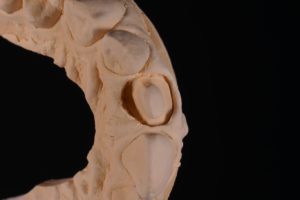

抜髄されてあった歯は打撲による外傷で歯が折れた過去があり、舌側に欠けて大きく歯が欠損していました。そこで、テンポラリークラウンにて歯肉のマネジメントを行い、シリコン印象材により丁寧に印象採得することで適合の良いクラウンを作ることができました。

また、模型上で事前にシミュレーションをすることで、ダイレクトボンディングにより欠けた部分の形態の再現が精度良くでき、審美的にも満足の行く治療となりました。